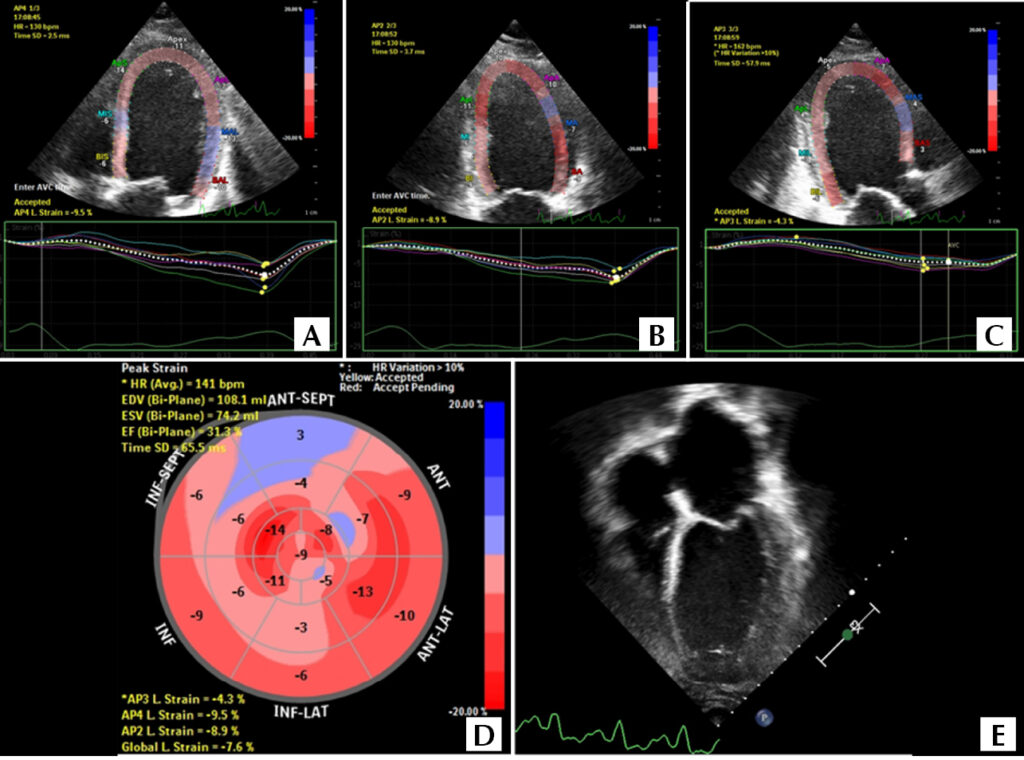

Como eu faço Avaliação Ecocardiográfica do Paciente Oncológico Pediátrico

A oncologia pediátrica teve grandes avanços nas últimas décadas devido ao desenvolvimento de protocolos de tratamentos mais eficazes, com sobrevida livre de doença em 5 anos superando 80%. No entanto, apesar da melhora nas taxas de sobrevida, os riscos cardiovasculares decorrentes dessas terapias são de cinco a seis vezes maiores quando comparados aos da população pediátrica geral., Assim, os eventos cardiovasculares, como infarto agudo do miocárdio, insuficiência cardíaca e acidente vascular cerebral, são a maior causa de morte não oncológica nesses pacientes.

A cardiotoxicidade é definida como qualquer dano estrutural ou funcional do coração e da circulação durante ou após o tratamento oncológico. Os responsáveis por essas alterações podem ser os agentes quimioterápicos, a radioterapia ou mesmo a própria doença (). Sua manifestação pode se dar com insuficiência cardíaca sintomática ou não, alterações do pericárdio, arritmias, eventos tromboembólicos, hipertensão arterial e doenças valvares e coronarianas., Pode também ser determinada pelo tempo de sua apresentação, sendo dividida em: